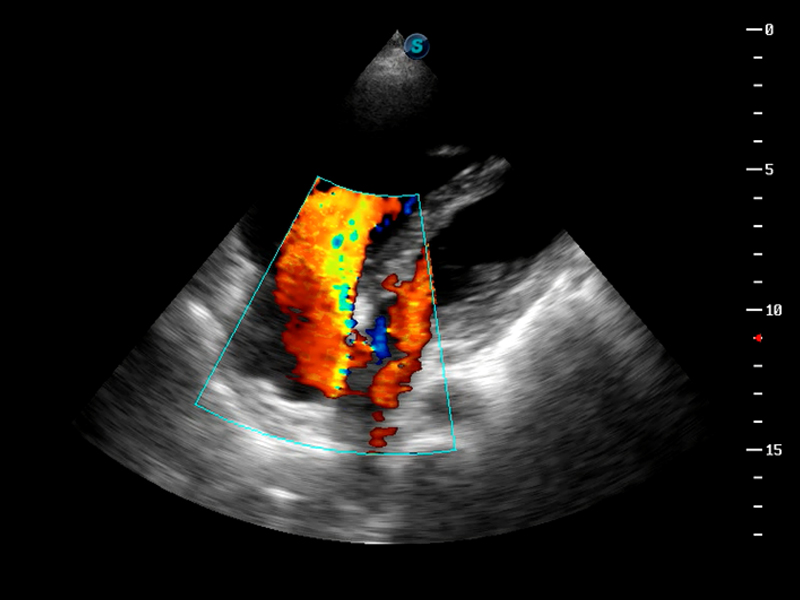

S9便携式彩色多普勒超声诊断仪是美狮贵宾会官网研发的高端便携彩超设备,外观设计新颖、产品性能卓越。S9在便携超声领域采用了突破传统的触摸屏交互设计,并以先进的软件硬件技术和设计理念,为您带来清晰的图像质量、稳定的工作性能和便捷的操作体验。

AutoC智能血流追踪